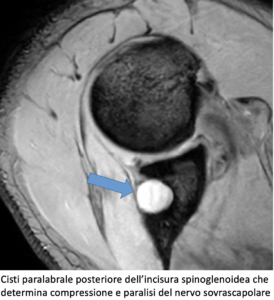

- All’incisura spinoglenoidea (paralisi isolata del muscolo infraspinato).

- Cisti paralabrali o gangli associati a lesioni del labbro glenoideo.

Quando la compressione avviene a livello spinoglenoideo, si osserva una paralisi isolata del muscolo sottospinato, con debolezza della sola extrarotazione e abduzione conservata.

- Risonanza magnetica (RM): individua masse compressive, cisti paralabrali, anomalie anatomiche e segni di denervazione muscolare.

- Rimozione di cisti paralabrali o correzione di lesioni labrali.